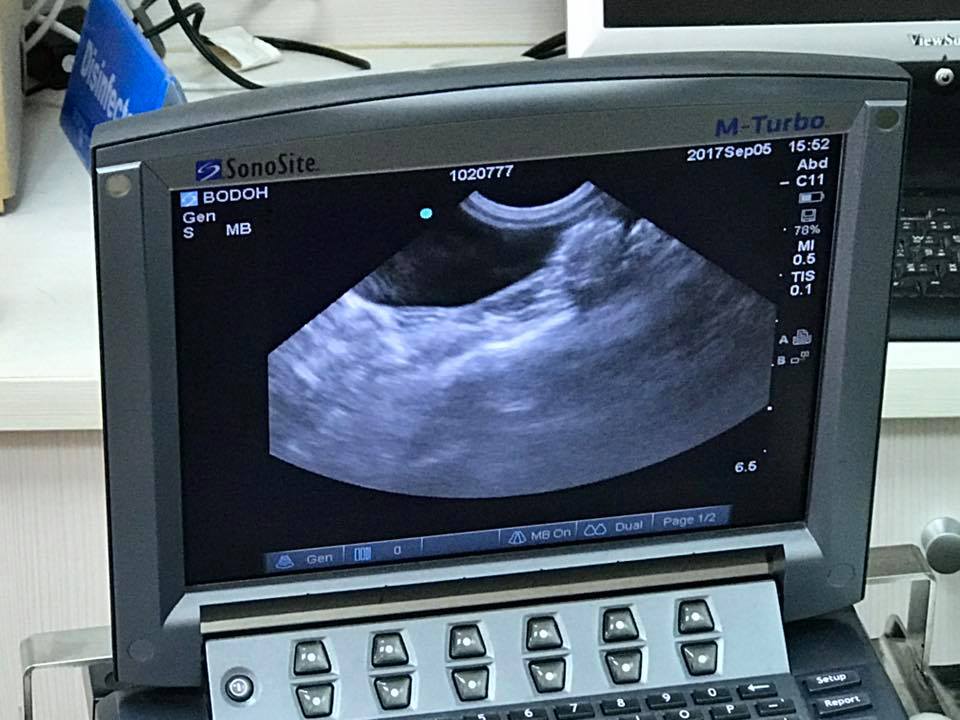

超音波檢查,沒有腹水,但淋巴結疑似腫大。